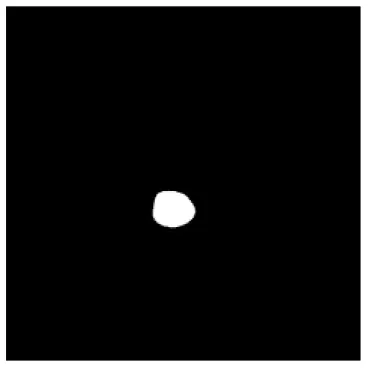

| Input CT image | Organs with manual segmentation | Organ with automatic segmentation | |

| Eye-R | ![]() | ![]() | ![]() |

The result of manual and automatic organ segmentation.